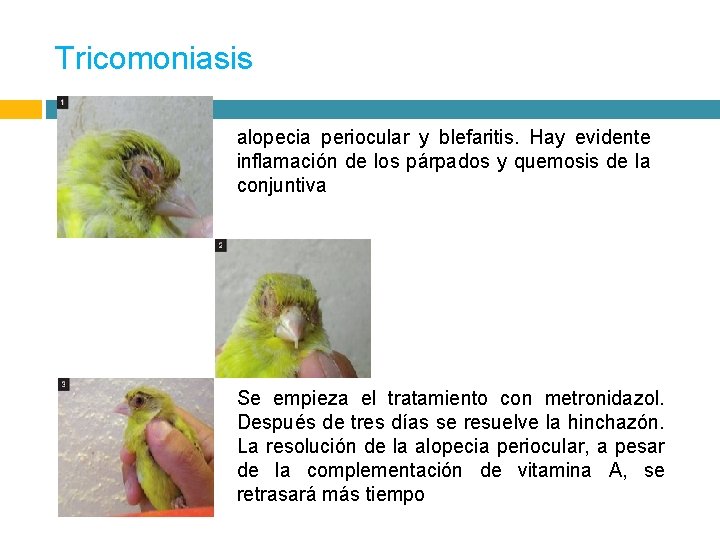

Tricomoniasis alopecia periocular y blefaritis. Hay evidente inflamación de los párpados y quemosis de la conjuntiva Se empieza el tratamiento con metronidazol. Después de tres días se resuelve la hinchazón. La resolución de la alopecia periocular, a pesar de la complementación de vitamina A, se retrasará más tiempo